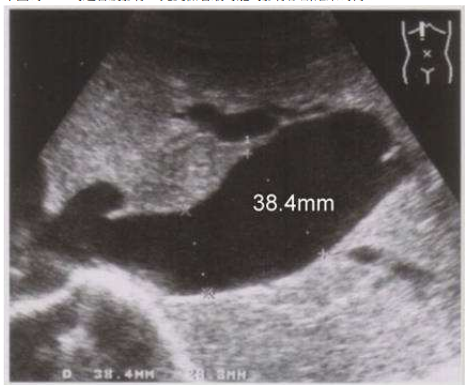

66.下圖為 IVC 的超音波影像,此受檢者最可能的影像診斷結果為何?

(A)right cardiac insufficiency (B)SVC syndrome (C)normal cardiac function (D)IVC thrombus